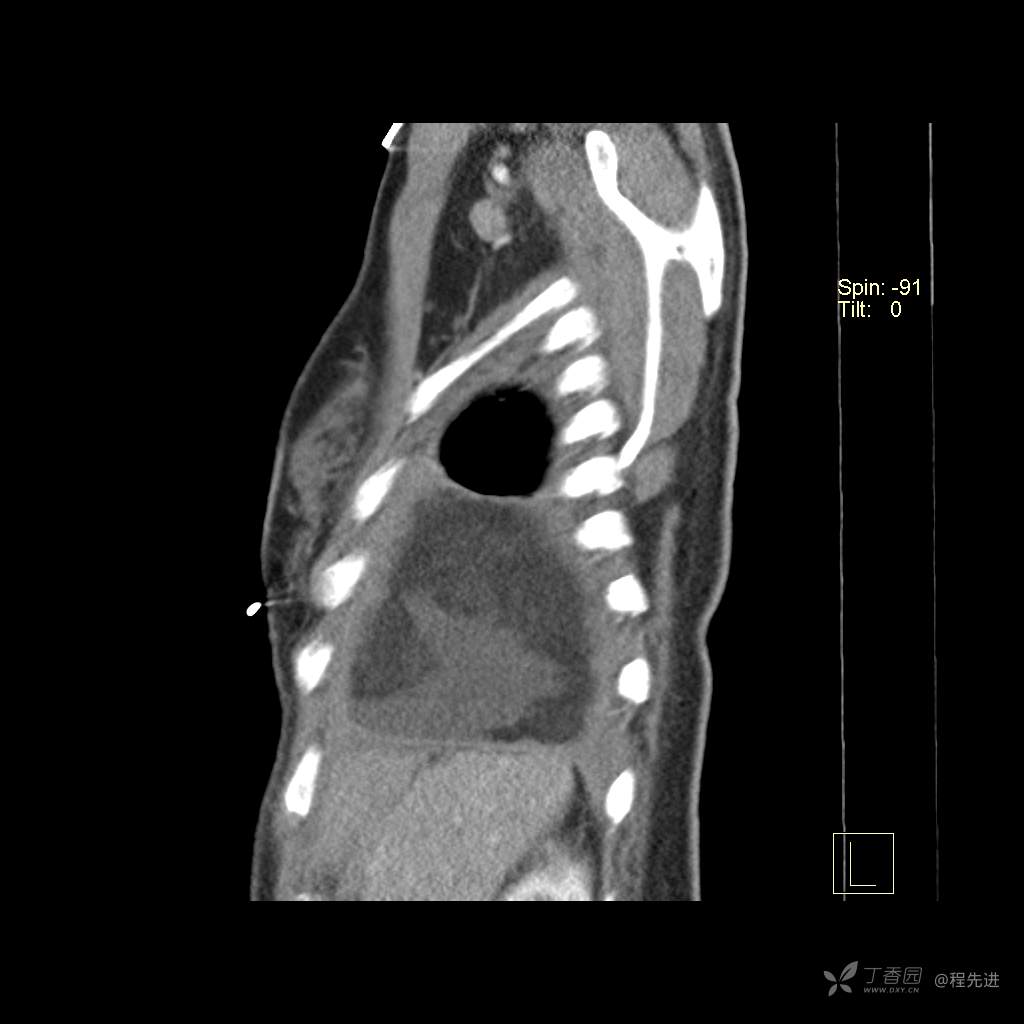

患者性别:女

患者年龄:51岁

简要病史:胸闷半年